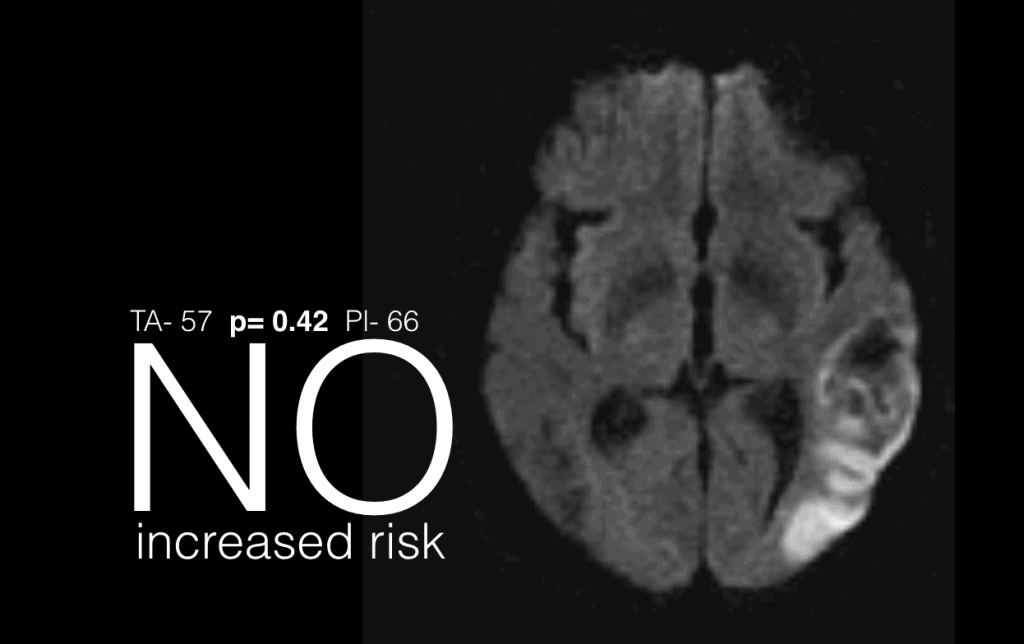

Construct a slide for each single data point that requires emphasis or explanation. It is important to re-state that a presentation is not the forum to saturate the audience with data, rather to concentrate on the message (p1) for the specific audience and illustrate that appropriately. In this example, if the segment being discussed is risk of stroke within the study group, this is best illustrated with a single, easily interpreted, memorable and clear slide. Images convey deep meaning and simple phrases overlaid give clarity.

Data slides must be easily interpreted, memorable and clear. Simple design rules can achieve this such that the single message of a section is readily available and the audience is not distracted by diverse information not pertinent to the message being delivered at that point. As an example, is there increased risk of acute haemorrhagic stroke with the use of tranexamic acid? Which slide made that clear to you? Clear data slides are not simplistic, not patronising to the audience and not about dissembling; they are about maintaining clarity and retention of message.